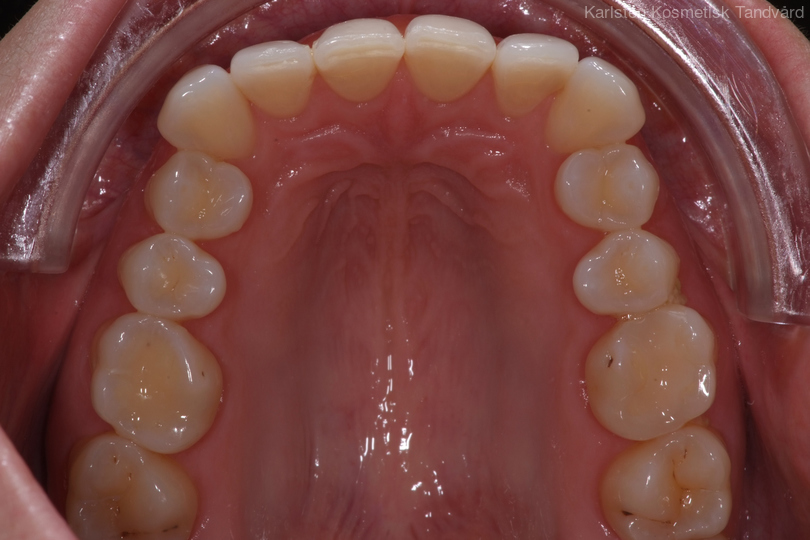

Tandreglering 5

32-årig kvinna som tycker att hon bara visar sina framtänder. En utjämning och vidgning av tandbågen med 8 månaders genomskinliga Invisalignskenor, gav henne ett fint leende.